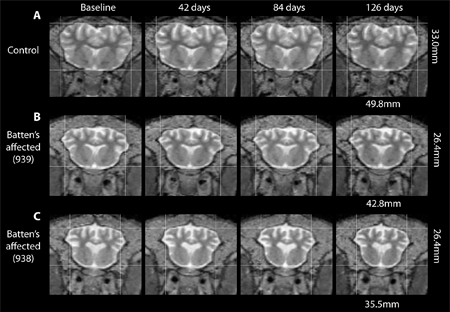

Researchers are conducting a research study on CLN3, Batten disease a neurodegenerative disease, with typical onset in children to identify markers of disease and to better understand CLN3 and how it develops over time. If you have Juvenile Neuronal Ceroid Lipofuscinosis, (CLN3, Batten disease), you may be eligible. Study-related tests and procedures are provided at no cost. Refer to study # 18-CH-0002.